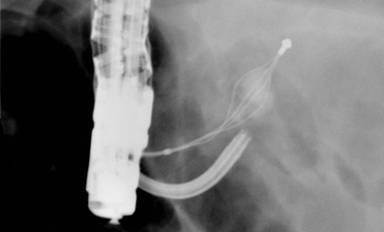

The decision was then made to utilize the mother-baby system and insert a FCP-9P Therapeutic Choledochofiberscope (Pentax of America, Montvale, NJ, USA) baby scope alongside the duodenoscope’s mother/working channel. A laser lithotripter was introduced into the pancreatic duct via the baby scope. The stone fragment at the tip of the basket was easily visualized. It was then targeted for lithotripsy. Laser energy was applied at a level of 1 J and frequency of 10 Hz. This successfully fulgurated the stone (Figure 2).

|

Figure 2. Pancreatic stone pieces in basket after laser lithotripsy. |